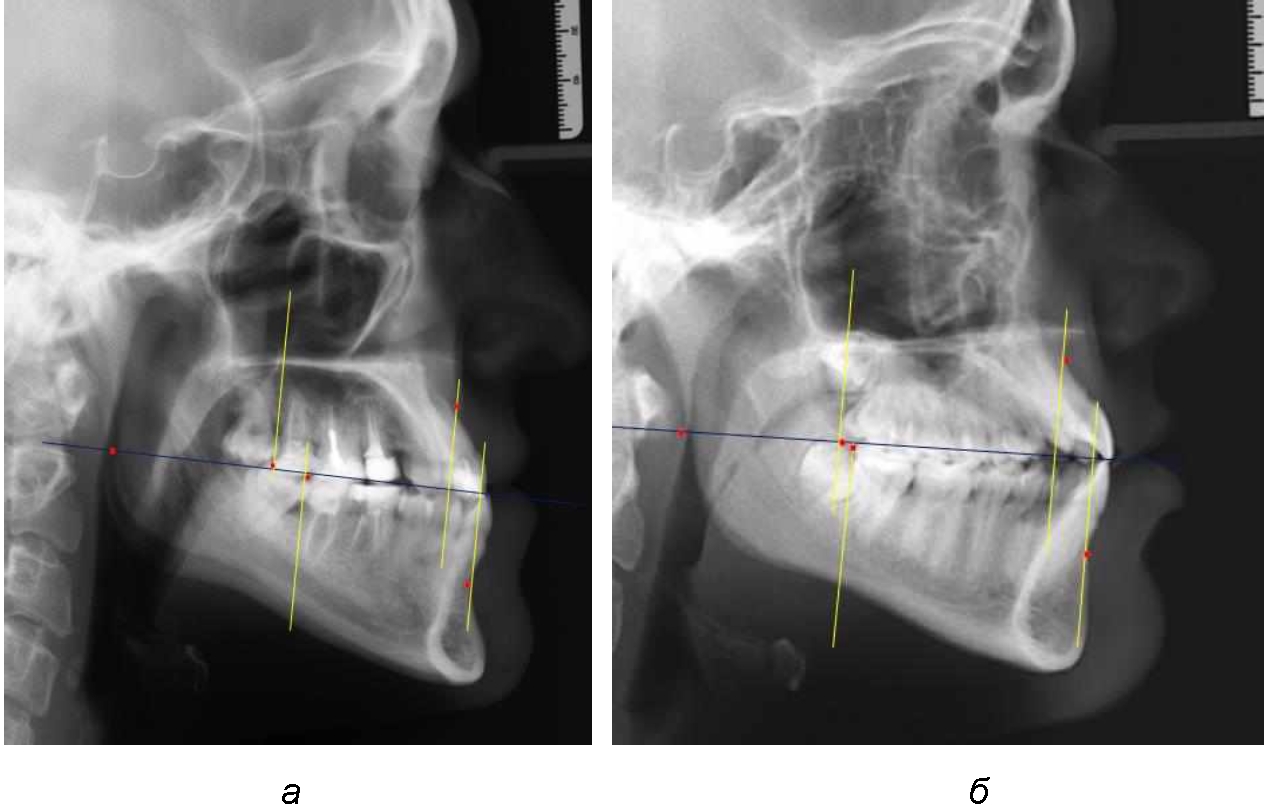

Расстояние от конструируемой точки окклюзионной плоскости на ветви челюсти («rmРOcP») до апикальных точек Downs на обеих челюстях также коррелировало между собой, и средняя величина различия показателей составляла (1,23 ± 0,69) мм. Проекция нижней апикальной точки на окклюзионную линию, как правило, располагалась несколько кпереди проекции верхней апикальной точки, на величину около 1 мм, что соответствовало оптимальным данным Wits-анализа.

Аналогичное расстояние было отмечено и при расположении дистальных окклюзионных точек верхней и нижней челюсти (рис. 2).

Рис. 2. Положение апикальных точек и челюстей при нормопозиции (а), антепозиции (б) и ретропозиции (в) верхней челюсти